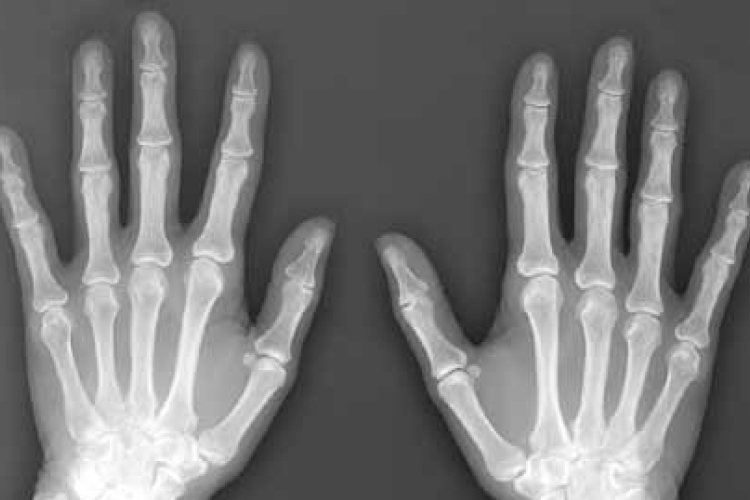

A magzatvízben lévő őssejtek újjáéleszthetik az öregedő és gyenge csontokat - állítják brit kutatók, akik szerint felfedezésük segíthet genetikai betegséggel született gyerekeken, idős embereken és űrhajósokon is.